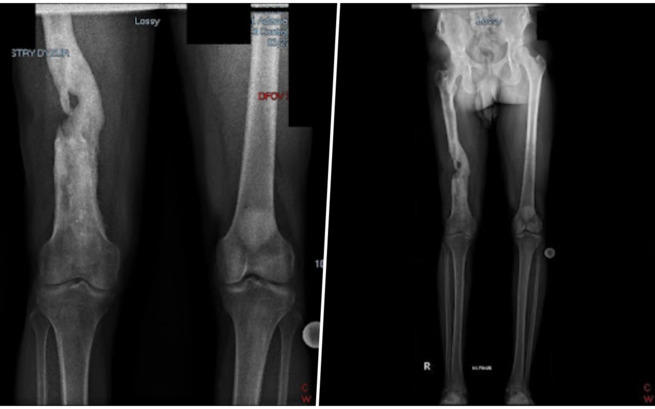

Kingsley 10 lat temu przeżył koszmar, od którego wszystko się zaczęło. Wracał do domu po służbie, w mundurze. Ktoś strzelił do niego od tyłu. Postrzał w prawe udo, strzaskana kość.

Kingsley pracował ciężko w polskiej fabryce, by choć trochę spłacić długi. Niestety szybko los ponownie go pokarał. Niedługo po przylocie do Polski ciężko zachorował i niemal zmarł. Znaleziono go nieprzytomnego z bólu, z wysoką gorączką i spuchniętą jak bania nogą.

Lekarze byli zgodni: jedyny ratunk to operacja.

Niestety wszyscy odmawiali leczenia. Ze względu na ryzyko, nie chcieli się podjąć przeprowadzenia operacji. A stan zapalny wciąż się rozwijał. My jednak chcieliśmy uratować mu życie i udało się. Szpital w Otwocku przeprowadził dwie skomplikowane operacje, które zakończyły się sukcesem.

Niestety Kingsley nadal wymaga regularnego leczenia i rehabilitacji, na które wciąż brakuje środków. Pieniędzy brakuje też na utrzymanie.